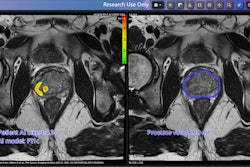

The £1 million program, certified to support cancer diagnosis, will allow for the platform to be used throughout a patient’s prostate cancer care journey with prostate cancer. Pi uses AI to combine insights from MRI and clinical tests.

The latest collaborative project will extend the Pi platform to further support active surveillance of patients living with prostate cancer. Hampshire Hospitals NHS Foundation Trust will lead the development of a new dataset of patients on active surveillance. Lucida Medical will use this to train new AI algorithms and develop additional workflows to extend the Pi platform. The University of Cambridge will then evaluate the platform with data from prostate cancer patients dating back over the last 10 years.